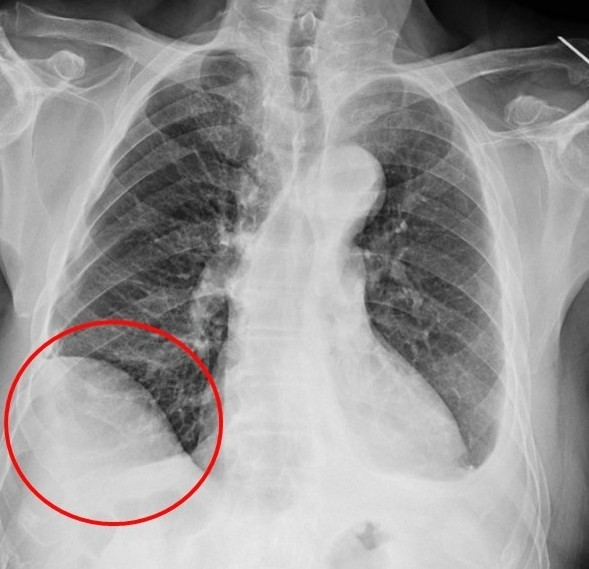

〔記者陳建志/台中報導〕75歲吳先生因肝臟細胞癌接受治療,沒想到又發現右下肺有一顆約1.2公分的腫瘤,因疑似肺癌轉介到胸腔及心臟血管外科,醫療團隊評估後決定進行手術切除,但因患者過去有車禍導致橫隔膜受傷,讓手術預期難度提高,決定採用健保給付的達文西機器人手術執行肺結節切除,順利切除腫瘤,並在術後第3天就出院返家休養。

廖啟耀表示,患者因外傷使手術困難度上升,過往使用傳統開胸手術或胸腔鏡手術在類似的病人,常因為分沾黏導致肺破損,需要較長的恢復時間,但是在進行達文西手術的過程中,不只術中沒有發生因為分沾黏常見的出血、肺破損等問題,患者在術後第2天便可拔除胸腔引流管,恢復順利。

廖啟耀強調,達文西手術是微創中的微創手術,可以幫助病人減少許多過往手術常見的問題,對病情複雜且困難的病人更是外科醫師的最佳選擇,不只創造更優秀的醫療環境,也幫助病人獲得更好的治療效果與生活品質。